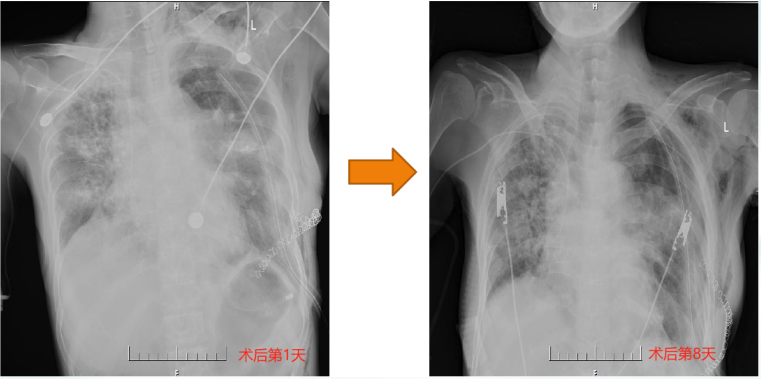

再次复查胸部CT术后1天相比左侧移植肺肺野非常清晰无新发病变(图14)

图片

14  复查胸部CT